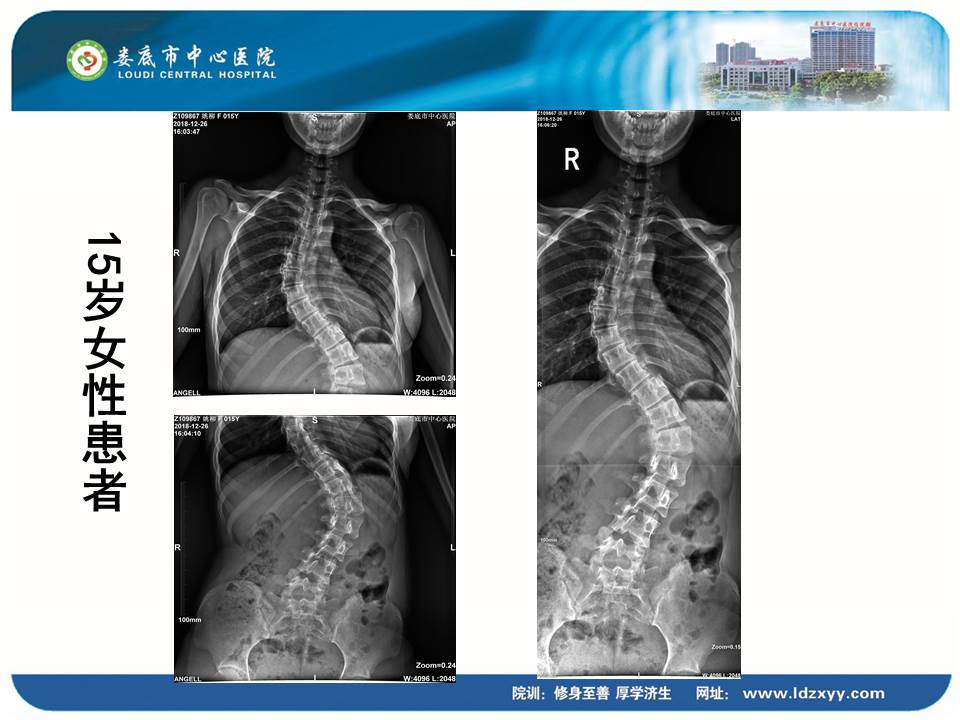

湖南影像学委员、娄底市放射学会副主任委员、娄底市中心医院放射科刘海潮副主任,则结合动态DR设备的全身拼接应用,分享了动态DR在骨科中的多项应用价值。刘海潮主任认为:由于常规DR的技术限制,长期以来放射科应用传统拍片并不能有效解决重叠部位的清晰显影,容易造成漏诊误诊,并且受制于成像视野的大小,不能有效显示脊柱四肢全长的整体结构及病变。而动态DR的17*17英寸大视野成像,配合900多万的高清像素及可视化的操作,较好地弥补了传统拍片的不足,而且初步实现了普放向精准诊断方向的转变。刘主任分享了动态DR在全脊柱摄影、全脊柱拼接、脊柱畸形,全下肢X线摄影、全下肢拼接、关节置换中的多项应用,通过站立负重位,快速、便捷摄取 2~3 张原始图像。在相邻两幅原始图像的重叠部分,对重叠图像的特征点迅速匹配,进行智能无缝融合处理,将数张有重叠部分的图像拼成一幅大型的无缝高分辨率图像。刘海潮主任评价:动态DR通过强大的图像后处理技术,比如边缘增强、灰阶处理,以及对对比度和锐利度的可调节性,大大提高了拼接影像的质量。

▲全身拼接应用示例